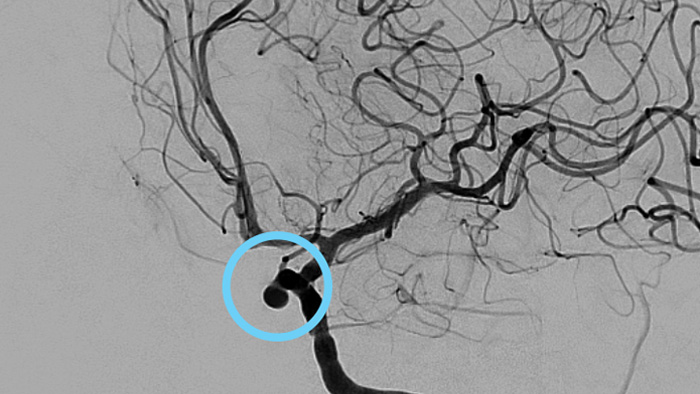

Fall mit freundlicher Genehmigung von Dr. Vitor Mendes Pereira, UHN, University of Toronto, Toronto, Kanada

Patient:

19. Juli 2012

13. Oktober 2014

Klinische Anwender verlassen sich auf die klassische DSA-Bildgebung als wichtigste Informationsquelle während des gesamten Eingriffs.

Nach der Aneurysmabehandlung werden die ordnungsgemäße Device-Positionierung und -Platzierung im Hinblick auf das Gefäß, den Aneurysmahals und den Aneurysmasack überprüft. AnerysmFlow ermöglicht die effiziente Messung der Wirksamkeit des eingesetzten Devices, sowie die Überprüfung auf mögliche arterielle Dissektionen, während sich der Patient noch auf dem Tisch befindet.

Sie können Veränderungen am Blutfluss im Aneurysma vor und nach der Behandlung durch Vergleich des Mittleren Aneurysma-Flussamplitudenverhältnisses (Mean Aneurysm Flow Amplitude Ratio, MAFA) vor und nach Einsetzen des Flow Diverters beurteilen.